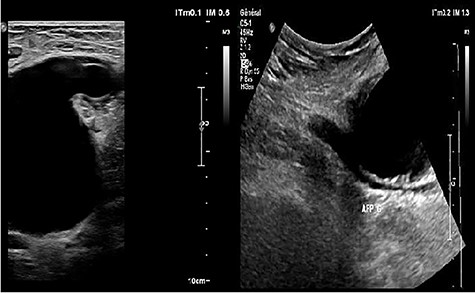

Ultrasonography (US) of the left thigh showed an aneurysmal dilatation of the SFA measuring 67 × 50 × 80 mm (Fig. 2) on the anterior aspect of the proximal third of the thigh. Computer tomography angiogram (CTA) confirmed a 64 × 80 × 87-mm PSA developed on the anterior side of the proximal left SFA (Fig. 3). The other arterial axes were healthy and normal. Supplementary imaging examinations did not identify any additional aneurysms.